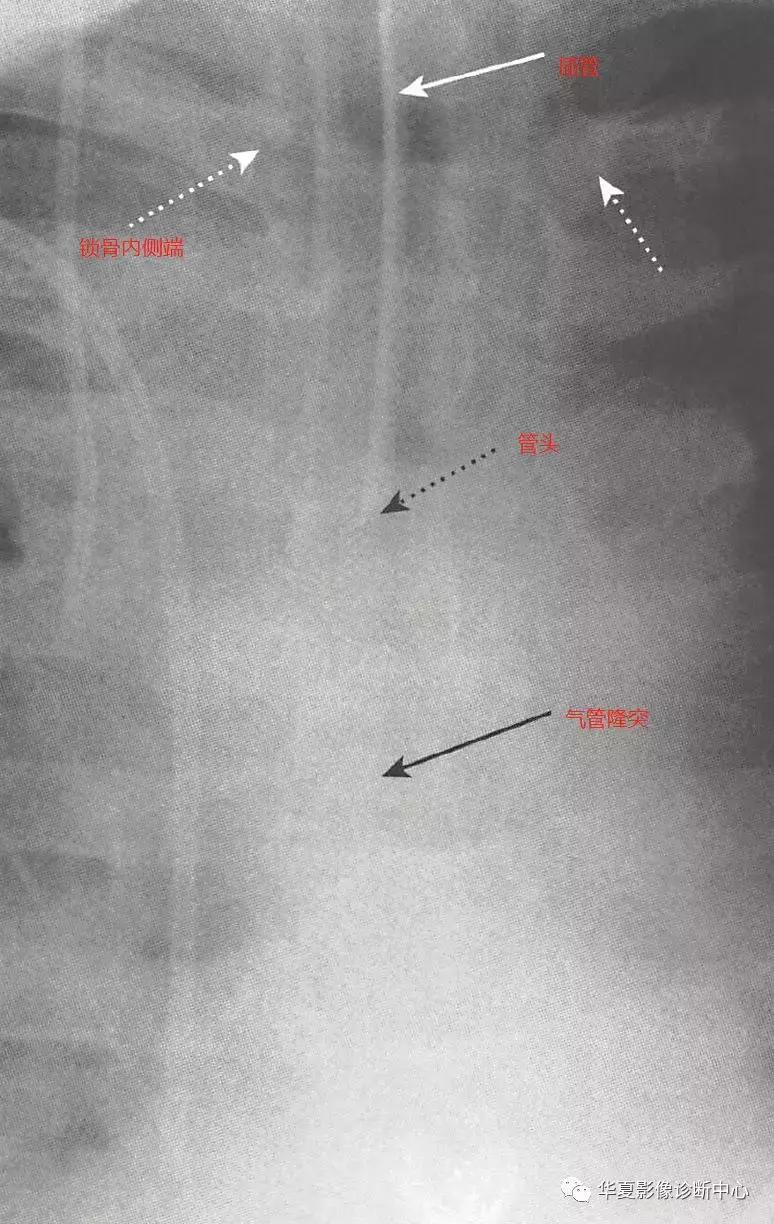

一、气管内插管(ETT)

气管内插管通常使用右不透射线标志条的无侧孔大口径导管(约1cm),管头通常为斜角形。患者头部位于正中位置(即下颌骨的底部,位于C5-6水平),此时气管插管管头距离气管隆突3-5cm。理想的ETT直径是气管宽度的1/2-1/3,如有充气气囊,应充满但不应扩张气管腔,最常见的位置异常是位于右主支气管或右肺下叶支气管,若管头位于颈部,有可能损伤声带。